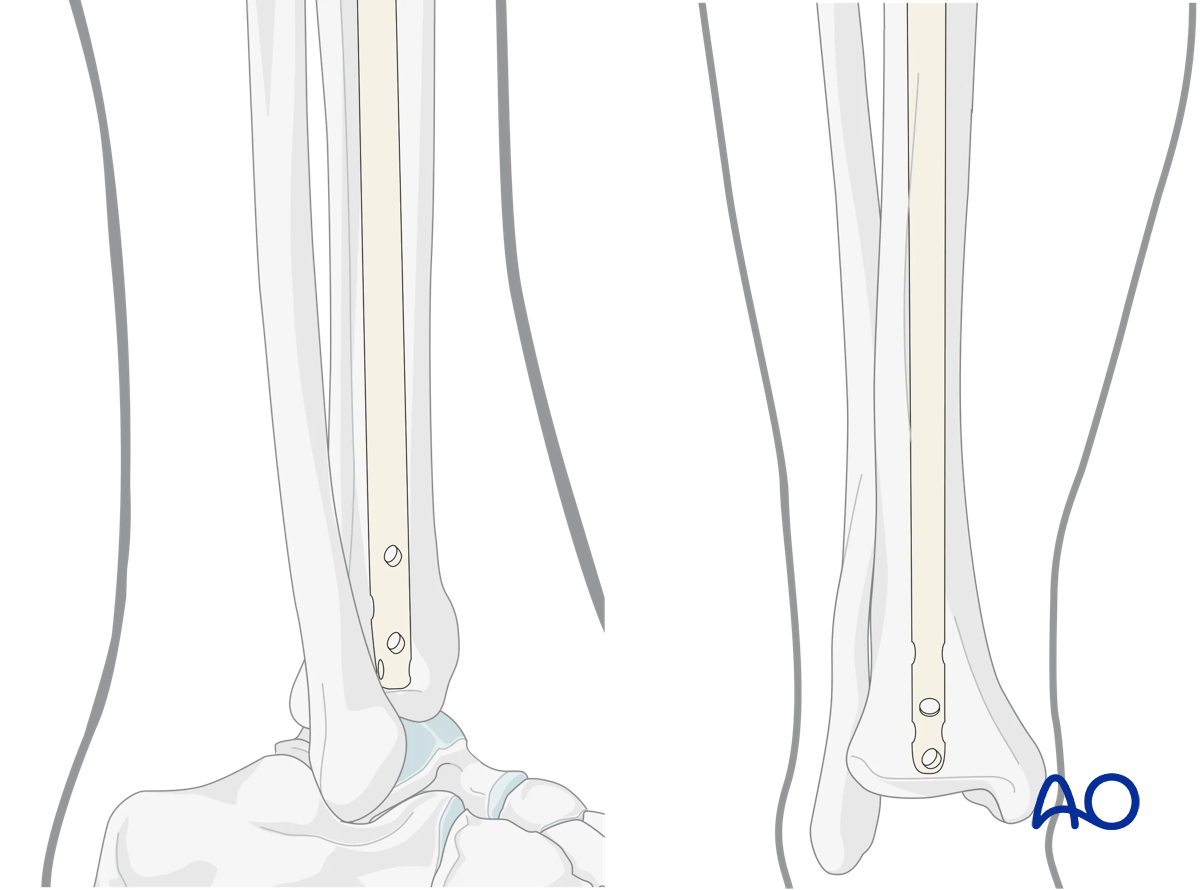

The tip of the nail should be placed in the center of the distal tibia, approximately at the level of the physeal scar (denser bone). Distal placement of the nail is particularly important for fractures below the medullary isthmus. Proper fracture alignment must be maintained by the surgeon, since at this level, passage of the nail does not reduce the fracture.

Suprapatellar intramedullary nailing, Insertion of the cannulated nail

Make sure that the proximal end of the nail is below the surface of the bone at the entry site, to decrease the risk of knee pain. Careful choice of nail length may be necessary, particularly for distal fractures, to ensure both distal fixation and proper length proximally.